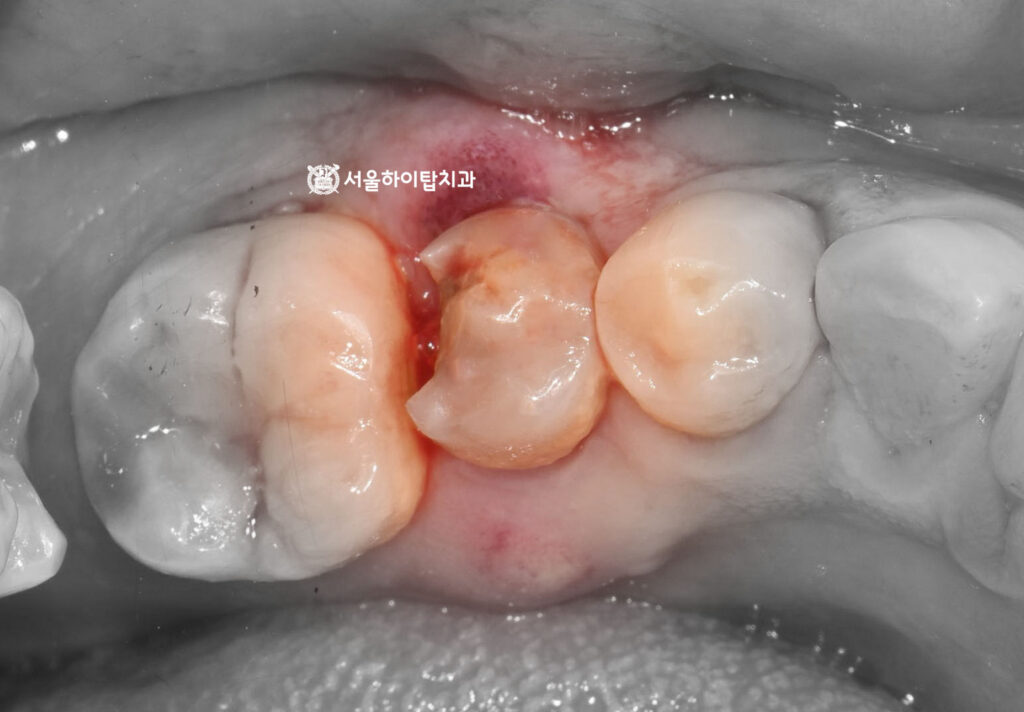

임플란트 가상 식립 시뮬레이션 진행

간석오거리역 치과 에서는

치수 감염이 확인된 상황으로,

잔존 치질의 양과 파절 범위를 고려했을 때

보존적 치료만으로는 장기적인 예후를

기대하기 어려운 상태로 판단되어

발치 후 임플란트를 계획할 수 있습니다.